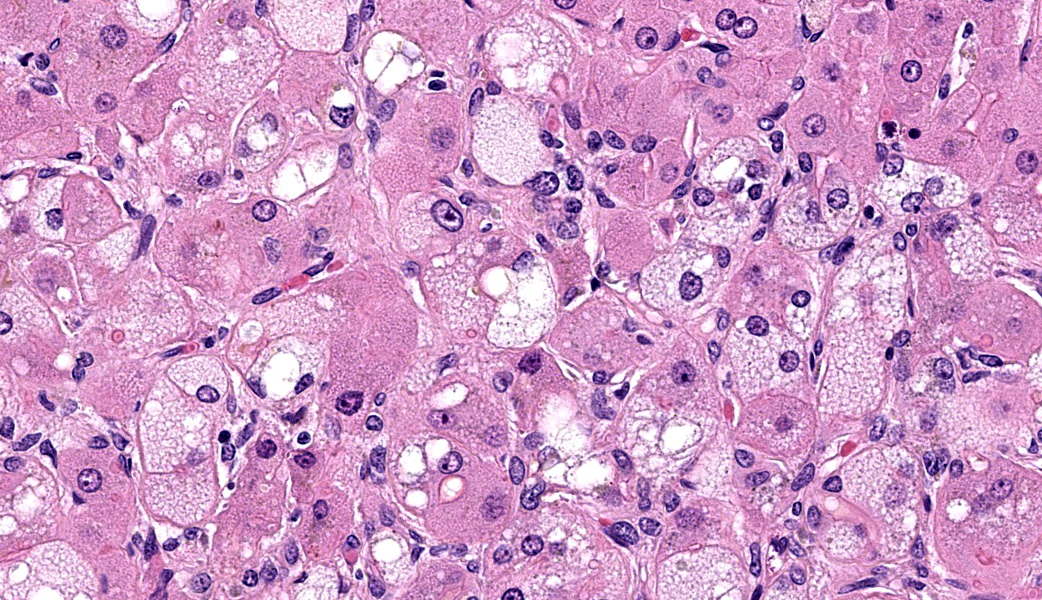

Microscopic Description: Approximately 60% of the hepatocytes in mostly periportal and centrilobular regions are markedly expanded by high numbers of microvesicular vacuolations (steatosis/lipid) and more rarely macrovesicular vacuolations or a mixture of the two. Sinusoids contain increased myofibroblasts (activated hepatic stellate cells) causing multifocal collapse of hepatocellular cord architecture. The myofibroblasts extend near portal areas, but distinct biliary hyperplasia is not appreciated. Occasionally hepatocytes are dissociated and composed of hypereosinophilic cytoplasm and lack a nucleus (necrosis). There are occasional binucleated hepatocytes. Canaliculi are multifocally, mildly expanded by tan to brown material (bile). Very rare lymphocytes are within sinusoids and in portal areas.

Contributor’s Morphologic Diagnoses: Severe, chronic, multifocal to coalescing microvesicular and macrovesicular steatosis with sinusoidal fibrosis and cholestasis

JPC Diagnoses: Liver: Hepatocellular micro- and macrovesicular lipidosis, chronic, multifocal to coalescing, severe, with marked stellate cell hyperplasia and cholestasis.

The contributor in this case provided a well-thought and informative writeup of hepatic lipidosis and hyperlipidemia, and much of what was discussed in conference is covered in their comment. Conference participants were, for the most part, readily able to achieve the reach the correct morphologic diagnosis in this case, but there was some speculation on the origin of the hyperplastic spindle cell population on the H&E. As mentioned by the contributor, there are two main possibilities: oval cells or stellate cells. Oval cells are bipotential progenitors of both hepatocytes and biliary ductular epithelial cells. Hepatic stellate cells, also called Ito cells, live primarily in the space of Disse, store Vitamin A, and can be activated into myofibroblasts following injury that will produce connective tissue components.3,8 Participants wondered if there was both oval cell and stellate cell hyperplasia in this case due to the presence of mild ductular reaction, cholestasis, and fibrosis, but unanimously agreed that there was at least stellate cell activation due to the fibrosis highlighted by a Masson’s trichrome. This is a difficult distinction to make on H&E alone.